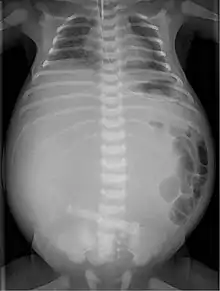

X-ray of a newborn with meconium pseudocyst resulting from bowel perforation. In this case the cause was atresia of the terminal ileum. There is a fine rim of calcification surrounding the big pseudocyst which shifts the other intestinal structures outwards.

Twenty percent of infants born with meconium peritonitis will have vomiting and dilated bowels on x-rays which necessitates surgery.

Meconium peritonitis is sometimes diagnosed on prenatal ultrasound[1] where it appears as calcifications[2] within the peritoneum.